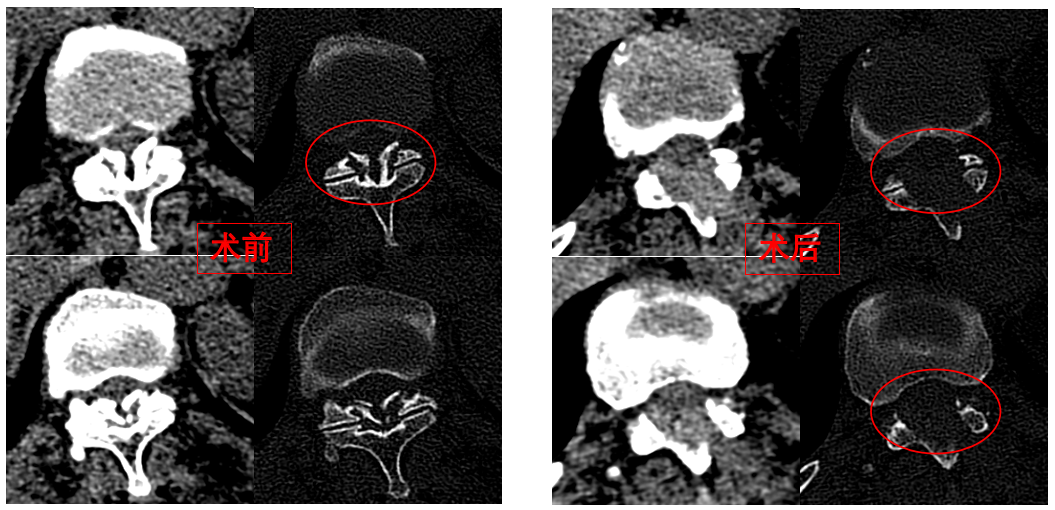

圖為卓瑪阿媽術(shù)前、術(shù)后胸椎CT照片對比。

華西醫(yī)院成辦分院骨科副主任醫(yī)師張斌接診后,憑借豐富的脊柱治療經(jīng)驗,立即安排卓瑪阿媽做了系列精密檢查,檢查結(jié)果顯示,阿媽胸椎11/12節(jié)段黃韌帶嚴重骨化,導致椎管顯著狹窄,脊髓受壓,確診為嚴重的“胸椎黃韌帶骨化癥”,如果不及時手術(shù)最終可能面臨癱瘓的風險。

手術(shù)歷時一個半小時,骨科脊柱微創(chuàng)團隊成功完整切除了壓迫脊髓的骨化黃韌帶,徹底解除了卓瑪阿媽的脊髓壓迫。手術(shù)過程順利,手術(shù)切口僅1厘米。